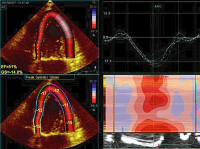

Strainanalyse

Abbildung 8: Strainanalyse (offline) der Raumforderung. Keine intrinsische Kontraktilität (rote Linie) im Vergleich zum linken und rechten Ventrikel.